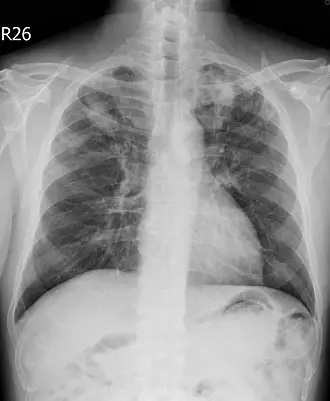

吳先生 45歲,不抽菸,因咳嗽 2 個月至門診就醫,胸部X光檢查結果如圖所示,最可能的診斷為何?

本題探討胸部X光片對於慢性咳嗽患者的影像判讀,重點在於鑑別慢性肺部病變中最具代表性的影像特徵,並與細菌性肺炎、間質性肺炎及肺癌進行比較,以確定最可能的診斷。

從正位胸部X光片觀察:

- 右上肺野可見不規則、斑片狀混濁,帶有節結性鈣化或纖維化影,邊緣不如典型肺葉性肺炎邊界清楚。

- 右上肺區伴有輕微容積減少,導致同側橫膈稍微抬高及肋間間距變窄。

- 未見單一大塊類圓形病灶或明顯實質腫塊,也無典型空氣支氣管徵。

- 無廣泛彌漫性細絲狀或磨玻璃影,排除主要以網狀或蜂窩狀為特徵的間質性肺疾患。

上述影像符合慢性、以上葉為主的纖維結節影與容積減少,提示以結核桿菌引起的再發型(post-primary)肺部病灶。